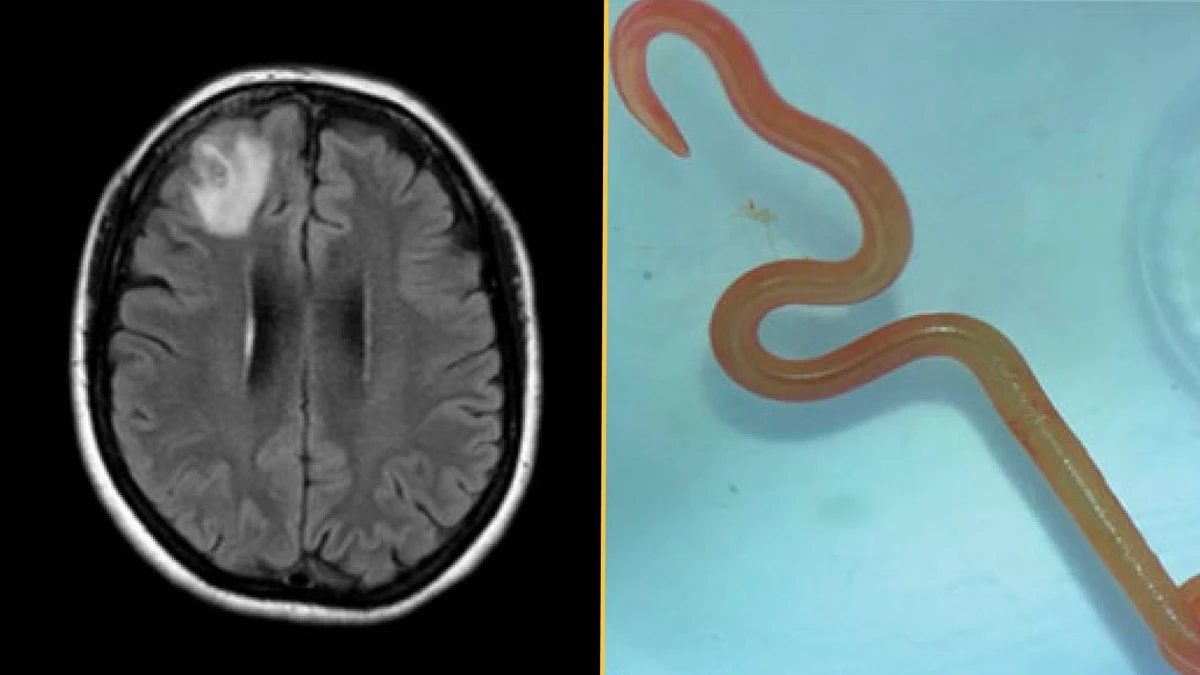

Výsledky odhalily jedinou lézi v pravém čelním laloku. Během operace, která měla tkáň prozkoumat, chirurgové objevili živého, jasně červeného červa. V těle pacienta nebyl nalezen žádný patogen, který by se v něm vyskytoval.

Tento případ byl prvním zdokumentovaným případem lidské infekce tasemnicí druhu Ophidascaris robertsi, parazitickým hlísticí pocházející z australských krajt. Larva o délce 80 mm, odstraněná z pacientčina mozku, představovala patogen, který lidé nikdy předtím neměli.

Během tří měsíců v roce 2022 se u pacientky začala objevovat zapomnětlivost a zhoršení deprese. MRI mozku ukázalo lézii v pravém čelním laloku.

V červnu 2022 chirurgové provedli otevřenou biopsii. V lézi pozorovali vláknitou strukturu a odstranili živého, pohyblivého helmintha (hlístici) o délce 80 mm.

- Histopatologie tkáně ukázala benigní zánětlivou dutinu s výraznou eozinofilií.

- Tým podmíněně identifikoval helmintha jako larvu třetího stadia Ophidascaris robertsi na základě jejího charakteristického červeného zbarvení a přítomnosti tří aktivních retromolárních pysků.

- Nezávislé PCR testování potvrdilo s více než 99,7% shodou identifikaci s izoláty Ophidascaris robertsi.